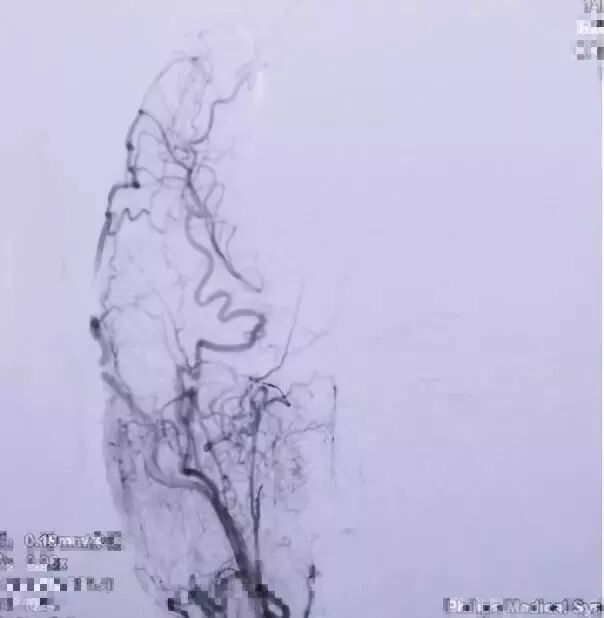

2017.04 DSA R-ICA

2017.04 DSA L-ICA